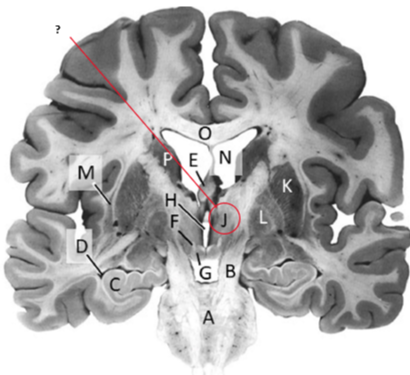

Name this ,state its function and the name of the structures closely associated with it.

Putamen.

Name this, state its function and its components[4 marks].

Globus Pallidus.

Components:

Name this and state its function.

Crus Cerebri.

Name this and state its function. Also, state all 3 fibres involved.

Basilar pons.